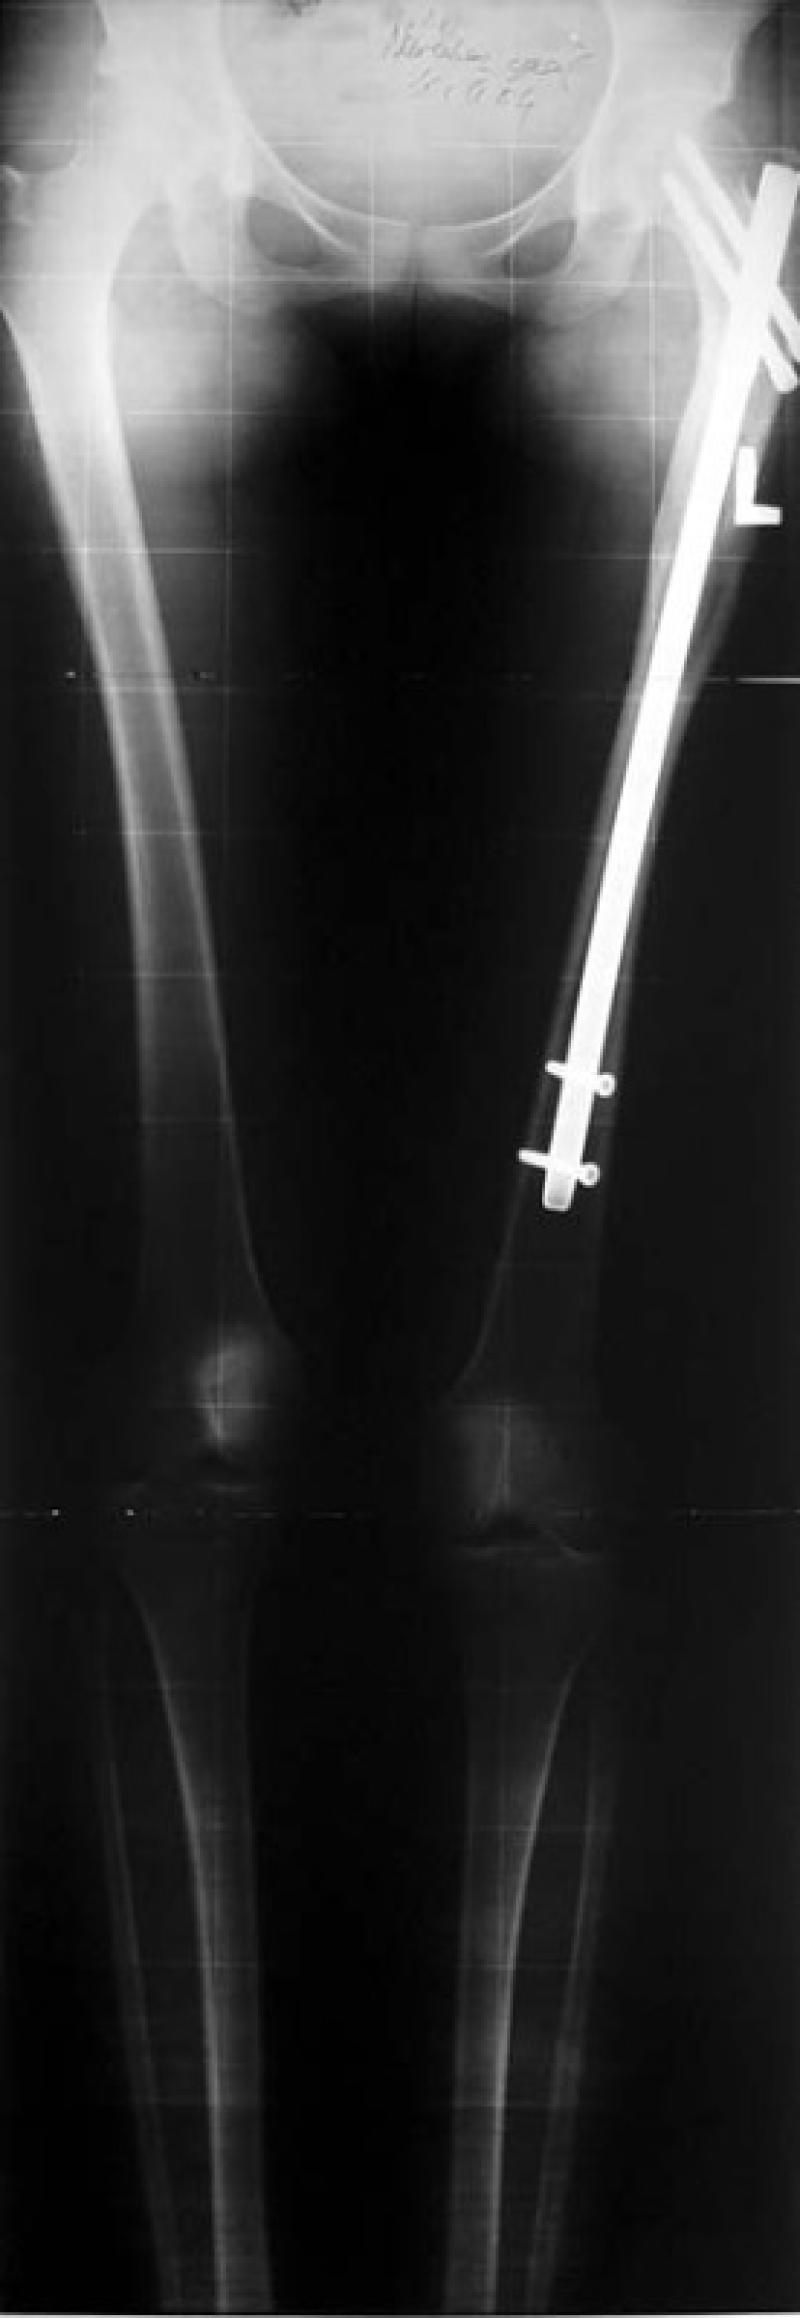

Holyfix Lengthening Technique

In this technique which is the advanced version of Wagner and De Bastiani methods, the nails mono-laterally fixed to the bone from outside are connected to Holyfix device for lengthening process. Up to 5 cm of lengthening in each limb - arm and leg - can be achieved.